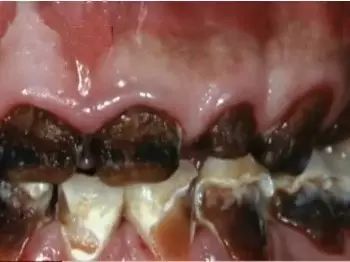

2.增加患齲齒的風(fēng)險(xiǎn)——牙牙不美觀

這副牙齒!!!雖然有點(diǎn)難以置信,但確實(shí)是真的牙齒,叫做“可樂(lè)牙”。眾所周知,碳酸飲料是一種酸性的液體,在與牙齒接觸時(shí)會(huì)腐蝕表層的牙釉質(zhì),會(huì)讓牙齒變得越來(lái)越敏感,無(wú)法承受正常程度的冷熱酸甜,長(zhǎng)此以往就會(huì)把一口好牙變成了“可樂(lè)牙”!生活中,有人用喝剩下的可樂(lè)刷馬桶、去水垢、去銹等,效果很好,就是因?yàn)榭蓸?lè)中所含有的磷酸對(duì)那些頑固的污垢具有瓦解作用。如果長(zhǎng)期大量地喝含有磷酸的飲料,對(duì)牙齒真的也具腐蝕性的破壞作用。

怪不得嬌嬌媽以前喝碳酸飲料,每次喝完都覺(jué)得牙齒澀澀的,一點(diǎn)都不光滑,原來(lái)是牙釉質(zhì)這層保護(hù)膜被飲料中的酸腐蝕啦!好可怕!